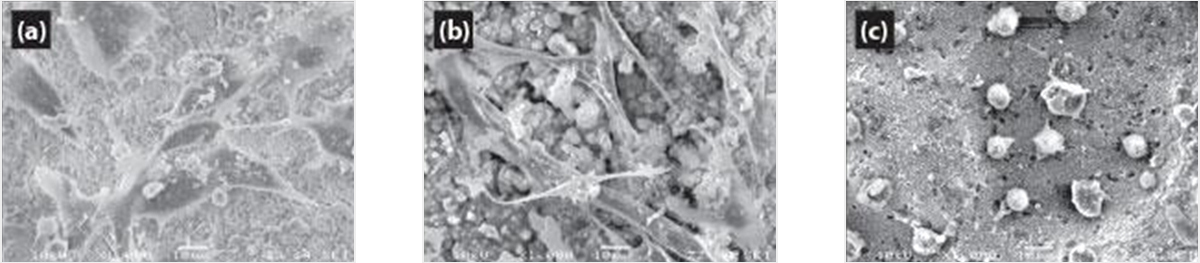

특허 받은 제조 기술인 엔도셈 MTA를 사용하여 우수한 생체 적합성을 보장합니다.

(a)엔도셈 MTA, (b)ProRoot, (C)IRM에 72 시간동안 배양 MG63 세포의 SEM 관찰(x1000)